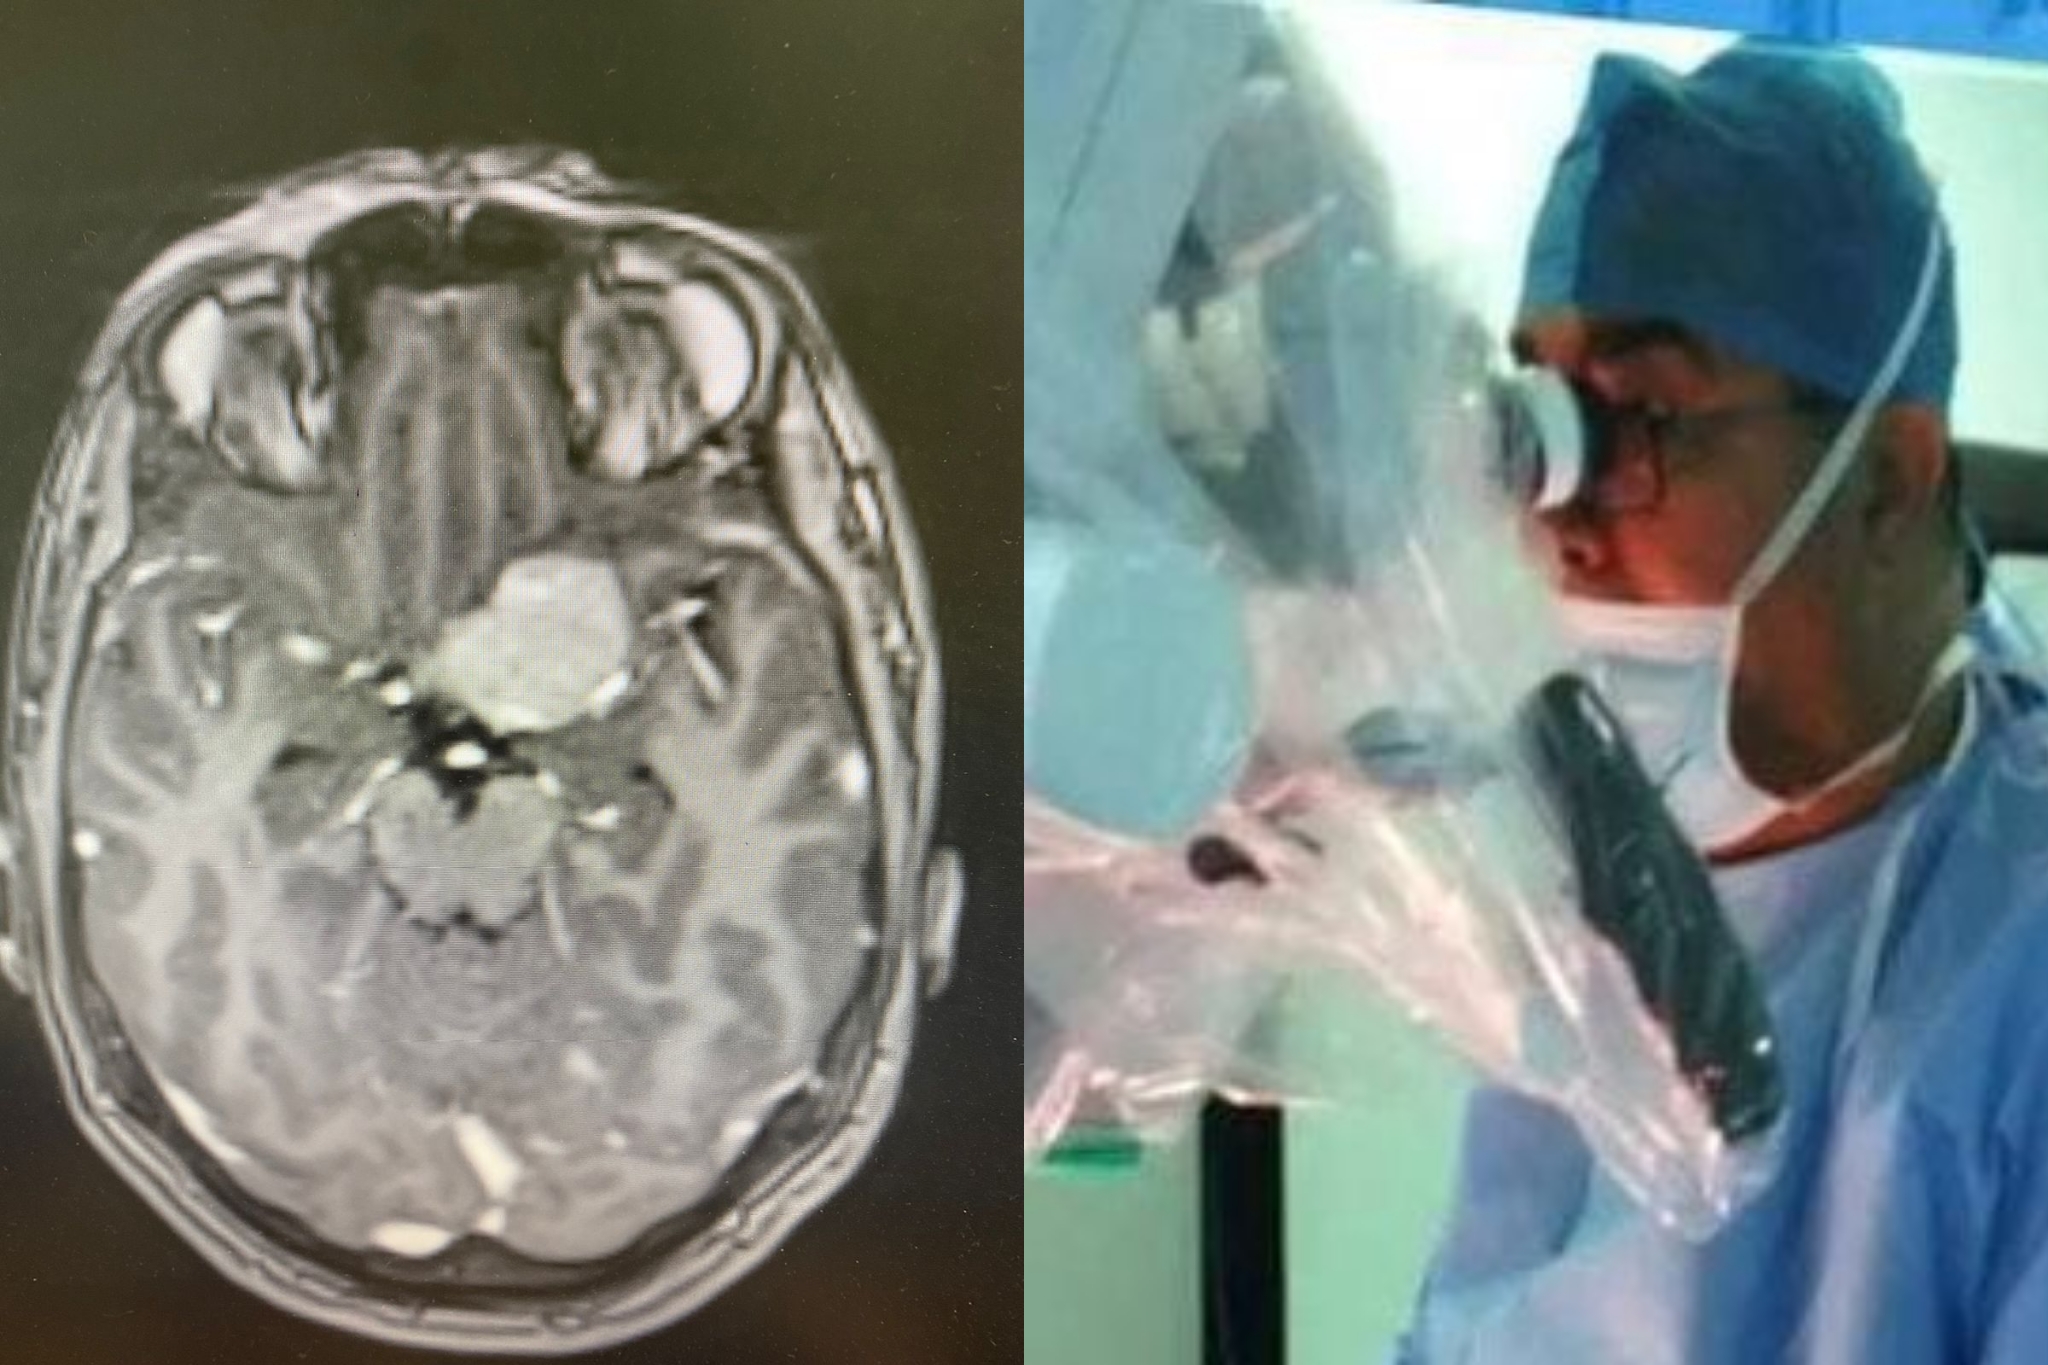

البيان الختامي لجمعية امراض الدماغ والأعصاب